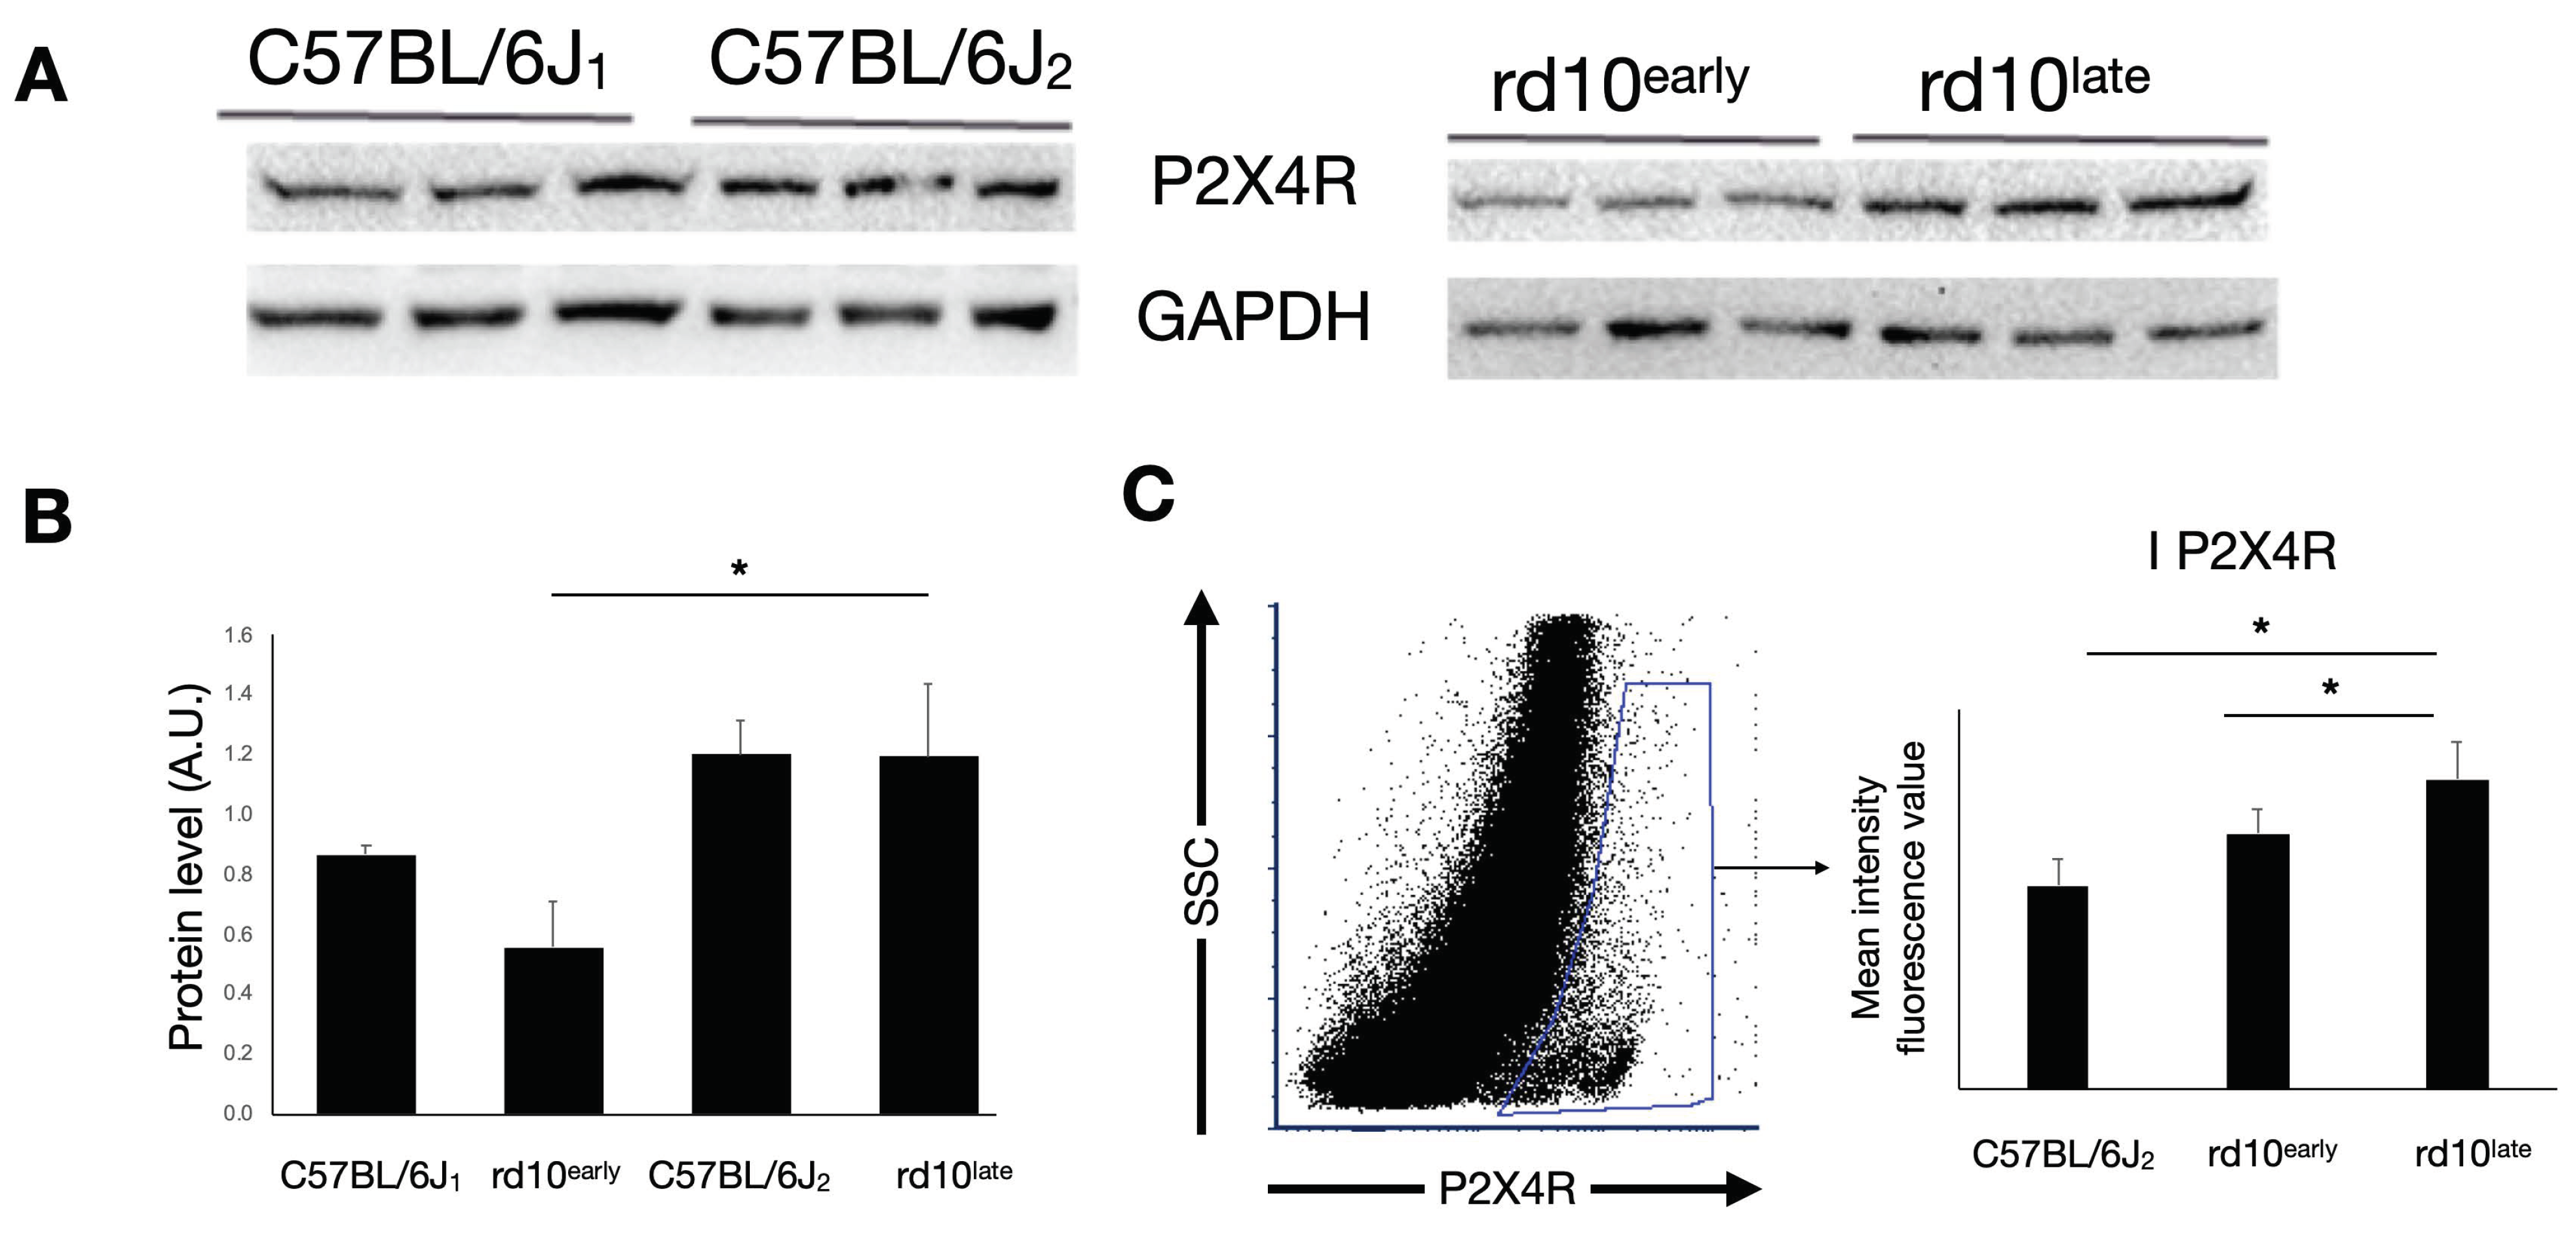

2.3. P2X4R Expression in rd10 Mice